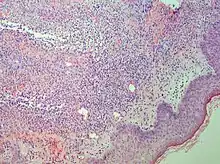

Interface dermatitis with vacuolar change

| Generally/Not otherwise specified | Typical findings, called "vacuolar interface dermatitis":[6]

![]() |

An interface dermatitis with vacuolar alteration, not otherwise specified, may be caused by viral exanthems, phototoxic dermatitis, acute radiation dermatitis, erythema dyschromicum perstans, lupus erythematosus and dermatomyositis.[2]